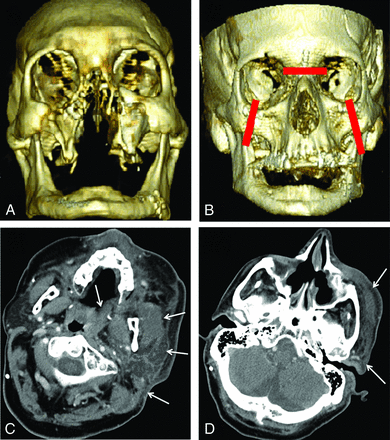

Patient 4 was attacked by a chimpanzee, sustaining severe facial injuries (Fig 4A). Full-face transplantation was performed in May 2011. Four weeks following the transplantation, the patient presented with facial swelling and erythema (Fig 4B). CT revealed a 4-cm conglomerate nodal mass with low-attenuation necrosis in the right submandibular region (Fig 4C). There was also a 1.8-cm fluid collection deep to the right zygoma with surrounding stranding and a 1.5-cm rim-enhancing fluid collection within the left submandibular region. CT-guided biopsy of the necrotic right submandibular mass was obtained, yielding inflammation without evidence of pus, rejection, or infection. CT-guided aspiration of the fluid collection deep to the native right zygoma was also performed (Fig 4D). Cultures grew Enterococcus species. The patient was placed on amoxicillin/clavulanic acid.

A, Preoperative 3D volume-rendered CT image of the patient whose face was mauled by a chimpanzee. B, Postoperative 3D volume-rendered CT image obtained for persistent fever and facial swelling 4 weeks following the surgery demonstrates facial swelling. C, Postoperative CT scan shows a necrotic-appearing right submandibular lymph node (arrow). CT-guided biopsy of this lymph node showed inflammation without evidence of infection or rejection. D, Postoperative CT also demonstrates a small fluid collection adjacent to the native right zygoma (circle), which was aspirated under CT guidance. Culture grew Enterococcus species.